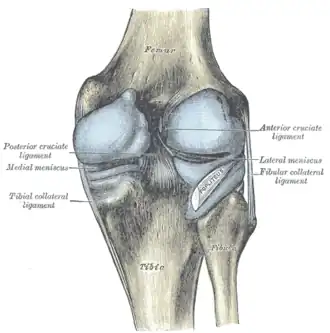

Ligaments

The ligaments surrounding the knee joint offer stability by limiting movements and, together with the menisci and several bursae, protect the articular capsule.[19]

Intracapsular

The knee is stabilized by a pair of cruciate ligaments. These ligaments are both extrasynovial, intracapsular ligaments.[20] The anterior cruciate ligament (ACL) stretches from the lateral condyle of femur to the anterior intercondylar area.[13] The ACL prevents the tibia from being pushed too far anterior relative to the femur.[13] It is often torn during twisting or bending of the knee.[21] The posterior cruciate ligament (PCL) stretches from medial condyle of femur to the posterior intercondylar area. This ligament prevents posterior displacement of the tibia relative to the femur.[13] Injury to this ligament is uncommon but can occur as a direct result of forced trauma to the ligament.

The transverse ligament stretches from the lateral meniscus to the medial meniscus. It passes in front of the menisci. It is divided into several strips in 10% of cases.[10]: 208 The two menisci are attached to each other anteriorly by the ligament.[22] The posterior (of Wrisberg) and anterior meniscofemoral ligaments (of Humphrey) stretch from the posterior horn of the lateral meniscus to the medial femoral condyle. They pass anterior and posterior to the posterior cruciate ligament respectively.[13][10]: 208 The meniscotibial ligaments (or "coronary") stretches from inferior edges of the menisci to the periphery of the tibial plateaus.

Extracapsular

The patellar ligament connects the patella to the tuberosity of the tibia. It is also occasionally called the patellar tendon because there is no definite separation between the quadriceps tendon (which surrounds the patella) and the area connecting the patella to the tibia.[23] This very strong ligament helps give the patella its mechanical leverage[24] and also functions as a cap for the condyles of the femur. Laterally and medially to the patellar ligament, the lateral and medial retinacula connect fibers from the vasti lateralis and medialis muscles to the tibia. Some fibers from the iliotibial tract radiate into the lateral retinaculum and the medial retinaculum receives some transverse fibers arising on the medial femoral epicondyle.[10]: 206

The medial collateral ligament (MCL a.k.a. "tibial") stretches from the medial epicondyle of the femur to the medial tibial condyle. It is composed of three groups of fibers, one stretching between the two bones, and two fused with the medial meniscus. The MCL is partly covered by the pes anserinus and the tendon of the semimembranosus passes under it.[10]: 206 It protects the medial side of the knee from being bent open by a stress applied to the lateral side of the knee (a valgus force).[10]: 206

The lateral collateral ligament (LCL a.k.a. "fibular") stretches from the lateral epicondyle of the femur to the head of fibula. It is separate from both the joint capsule and the lateral meniscus.[10]: 206 It protects the lateral side from an inside bending force (a varus force). The anterolateral ligament (ALL) is situated in front of the LCL.

Lastly, there are two ligaments on the dorsal side of the knee. The oblique popliteal ligament is a radiation of the tendon of the semimembranosus on the medial side, from where it is direct laterally and proximally. The arcuate popliteal ligament originates on the apex of the head of the fibula to stretch proximally, crosses the tendon of the popliteus muscle, and passes into the capsule.[10]: 206